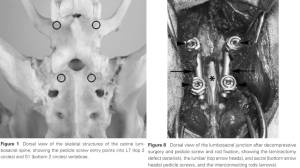

- Methoden

- Verplattung

- transartikuläre Schrauben durch Fasettengelenke

- Gewindepins + Knochenzement